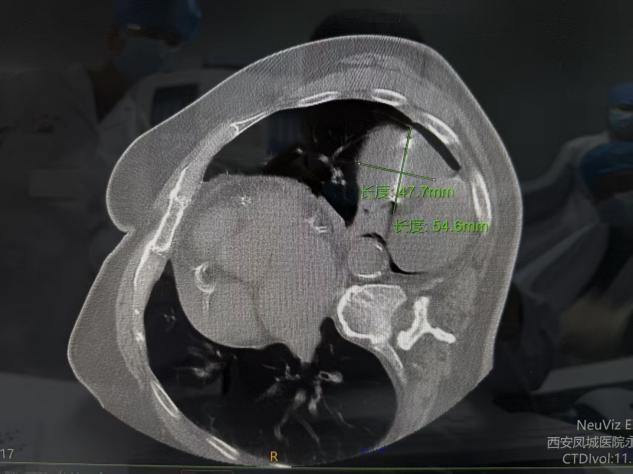

病例二

此次接受手术的两位患者,因身体基础状况、病灶位置等因素,均不适合传统外科手术治疗。胸外科开科后,第一时间组织团队对患者病情进行全面评估,联合医学影像科等科室开展MDT多学科讨论,为两位患者量身定制了个体化冷冻消融治疗方案。手术在局部麻醉下进行,在CT实时精准引导下,将超细冷冻消融针穿刺至病灶核心区域,通过超低温冷冻,精准摧毁病变细胞,同时最大程度保护周边正常组织和重要血管、神经。整个手术过程高效、微创,两位患者术中生命体征平稳,全程保持清醒且痛感轻微,皮肤上仅留针眼大小的创口。术后即刻复查影像显示,消融范围覆盖病灶,达到预期治疗效果。术后患者恢复迅速,2小时内即可下床活动,有效缩短了住院周期,患者及家属对治疗效果和就医体验均表示高度认可并送来锦旗感谢。